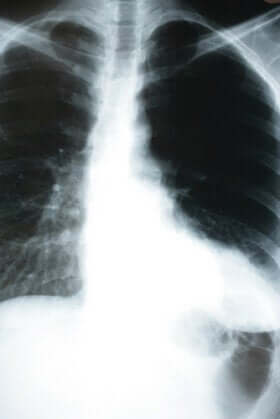

Doch bei einer stillen Lungenentzündung ist dies nicht der Fall. In verschiedenen Krankenhäusern in New York und Brasilien haben Ärzte viele Patienten mit einer stillen Lungenentzündung beobachtet, die sich in einem guten Zustand befanden. Erst durch die Messung der Sauerstoffsättigung oder durch eine Röntgenaufnahme des Brustbereichs konnten sie die Lungenentzündung erkennen.

Bei jedem kleinsten Verdacht empfiehlt es sich deshalb, die Sauerstoffsättigung im Blut zu messen und gegebenenfalls eine Röntgenaufnahme des Brustbereiches vorzunehmen. Dies ist insbesondere dann wichtig, wenn die betroffene Person Kontakt mit einem infizierten Menschen hatte oder wenn es sich um einen Patienten aus einer Risikogruppe handelt.